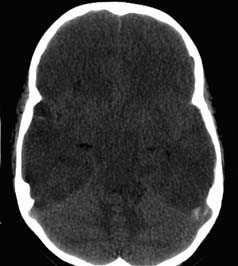

Применение компьютерной томографии в нейротравматологии существенно изменило представление о возможностях диагностики различных черепно-мозговых повреждений. КТ является в настоящий момент «золотым стандартом» - наиболее информативным методом обследования больных с черепно-мозговыми травмами и позволяет в самые короткие сроки судить о механизмах возникновения поражения мозга, его характере, распространенности, выраженности отека и дислокации мозга, а также динамике этих изменений.

- выявить наличие внутричерепной гематомы (её характер, локализацию, размеры),

- выявить наличие очага ушиба головного мозга (его локализацию, размеры, характер, наличие геморрагического компонента),

- выявить наличие диффузного или перифокального отека и его степени,